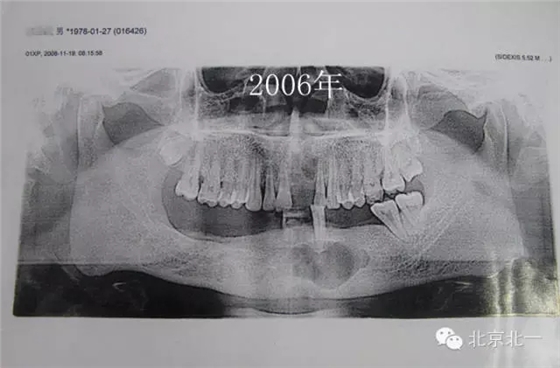

患者男,33歲,左下頜囊腫復發(fā)兩次就診。

圖一、初診時全景片